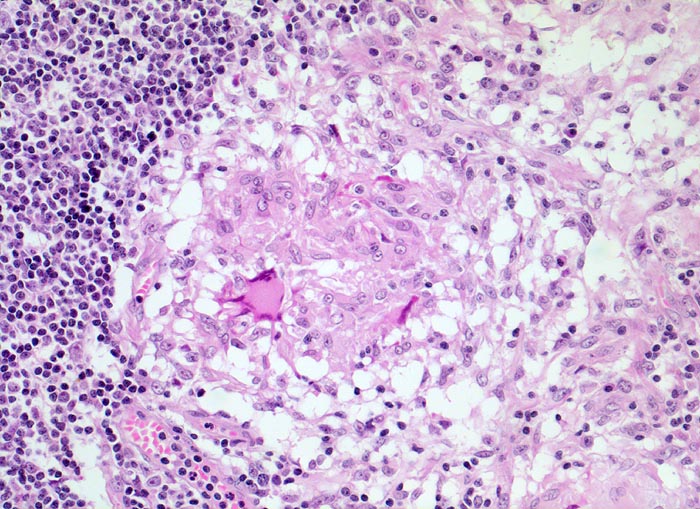

PathoPic ID 3938 - retikulozytär-abszedierende Lymphadenitis bei Katzenkratzkrankheit

retikulozytär-abszedierende Lymphadenitis bei Katzenkratzkrankheit

Entzündung infektiös

Lymphknoten, Axilla

Lymphatische Gewebe, KM, Milz

Neben zentral abszedierten Granulomen (hier nicht im Bild) finden sich auch epitheloidzellige

nicht nekrotisierende Granulome mit Riesenzellen.

Druckschmerzhafte Lymphknotenvergrösserung in der rechten Axilla 2 Wochen nachdem der Patient von seiner Katze an der rechten Hand gekratzt wurde.

Histologie

200